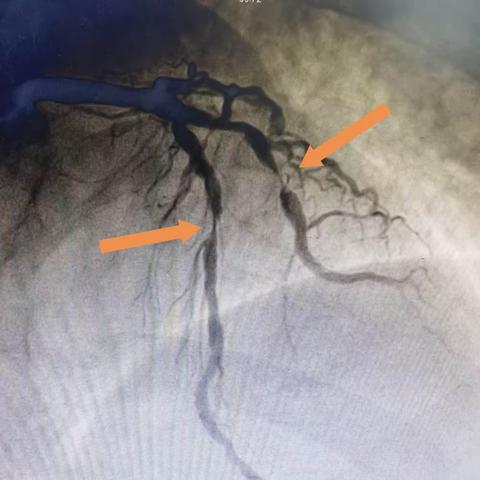

1例经皮冠状动脉介入治疗(PCI)的分享

生死时速--急诊PCI为急性心肌梗死患者开启绿色通道